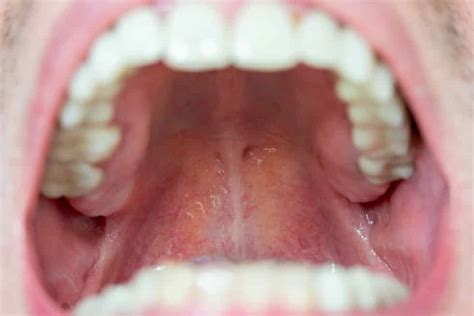

La inflamación del paladar es una condición en la que el tejido del paladar, la parte de la boca que forma el cielo de la cavidad oral, se inflama o hincha debido a una variedad de razones que mencionaremos más adelante.

El paladar se encuentra en la parte superior interna de la cavidad bucal. Por esto también se le llama popularmente como cielo o techo de la boca. Este se encarga de separar la cavidad nasal de la bucal. Se divide en dos partes que son el paladar óseo, que es la zona más dura ya que está formado por huesos, y el paladar blando, que está recubierto con una capa de mucosa. Este llega hasta la úvula en la parte posterior, a la que también se le conoce como campanilla. Es este el tejido el que impide que la comida pase hacia las fosas nasales y los pulmones.

El paladar sano tiene un color rosáceo y uno de los primeros síntomas de que hay un problema es el cambio de tonalidad; por lo general a un tono amarillo. Los síntomas de un paladar inflamado pueden decir mucho acerca de nuestra salud general. Aunque la mayoría de las veces no se trate de nada serio, otras sí indicará alguna enfermedad que deba tratarse a tiempo.